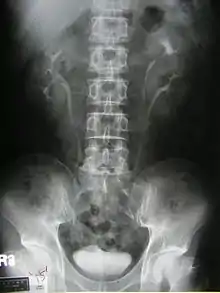

Duplicated ureter or Duplex Collecting System is a congenital condition in which the ureteric bud, the embryological origin of the ureter, splits (or arises twice), resulting in two ureters draining a single kidney. It is the most common renal abnormality, occurring in approximately 1% of the population.[1][2]

Diagnosis

Prenatally diagnosed hydronephrosis (fluid-filled kidneys) suggest post-natal follow-up examination. The strongest neo-natal presentation is urinary tract infection. A hydronephrotic kidney may present as a palpable abdominal mass in the newborn, and may suggest an ectopic ureter or ureterocele. In older children, ureteral duplication may present as: